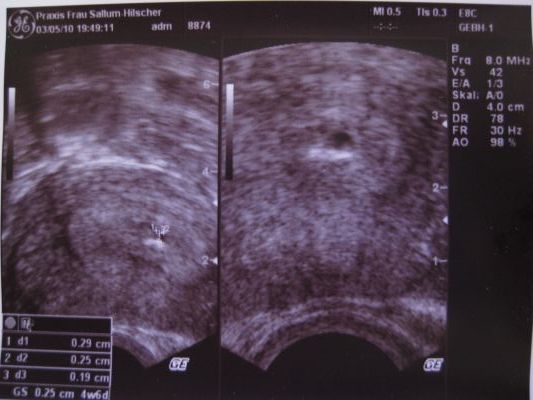

Chis, nagyon édes babód van!

Amilyen picike most, olyan szépen megnő, mire ki kell bújnia.